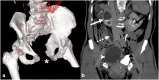

The presence of a duplicated urinary bladder and prostate has not been described. We report the case of a complete duplication of the urinary bladder and prostate, associated with one urethral meatus and a bifid urethra. A 68-year-old male presented with chronic lower urinary tract symptoms (LUTS), recurrent urinary tract infections, bladder stone removal and epispadias repair. Bladder duplication was incidentally found during imaging. Cystoscopy confirmed one meatus with two bladders and urethras, each with its own prostate. Transurethral resection of both prostates (TURP) was performed. This is the first reported case of complete duplication of both bladder and prostate.